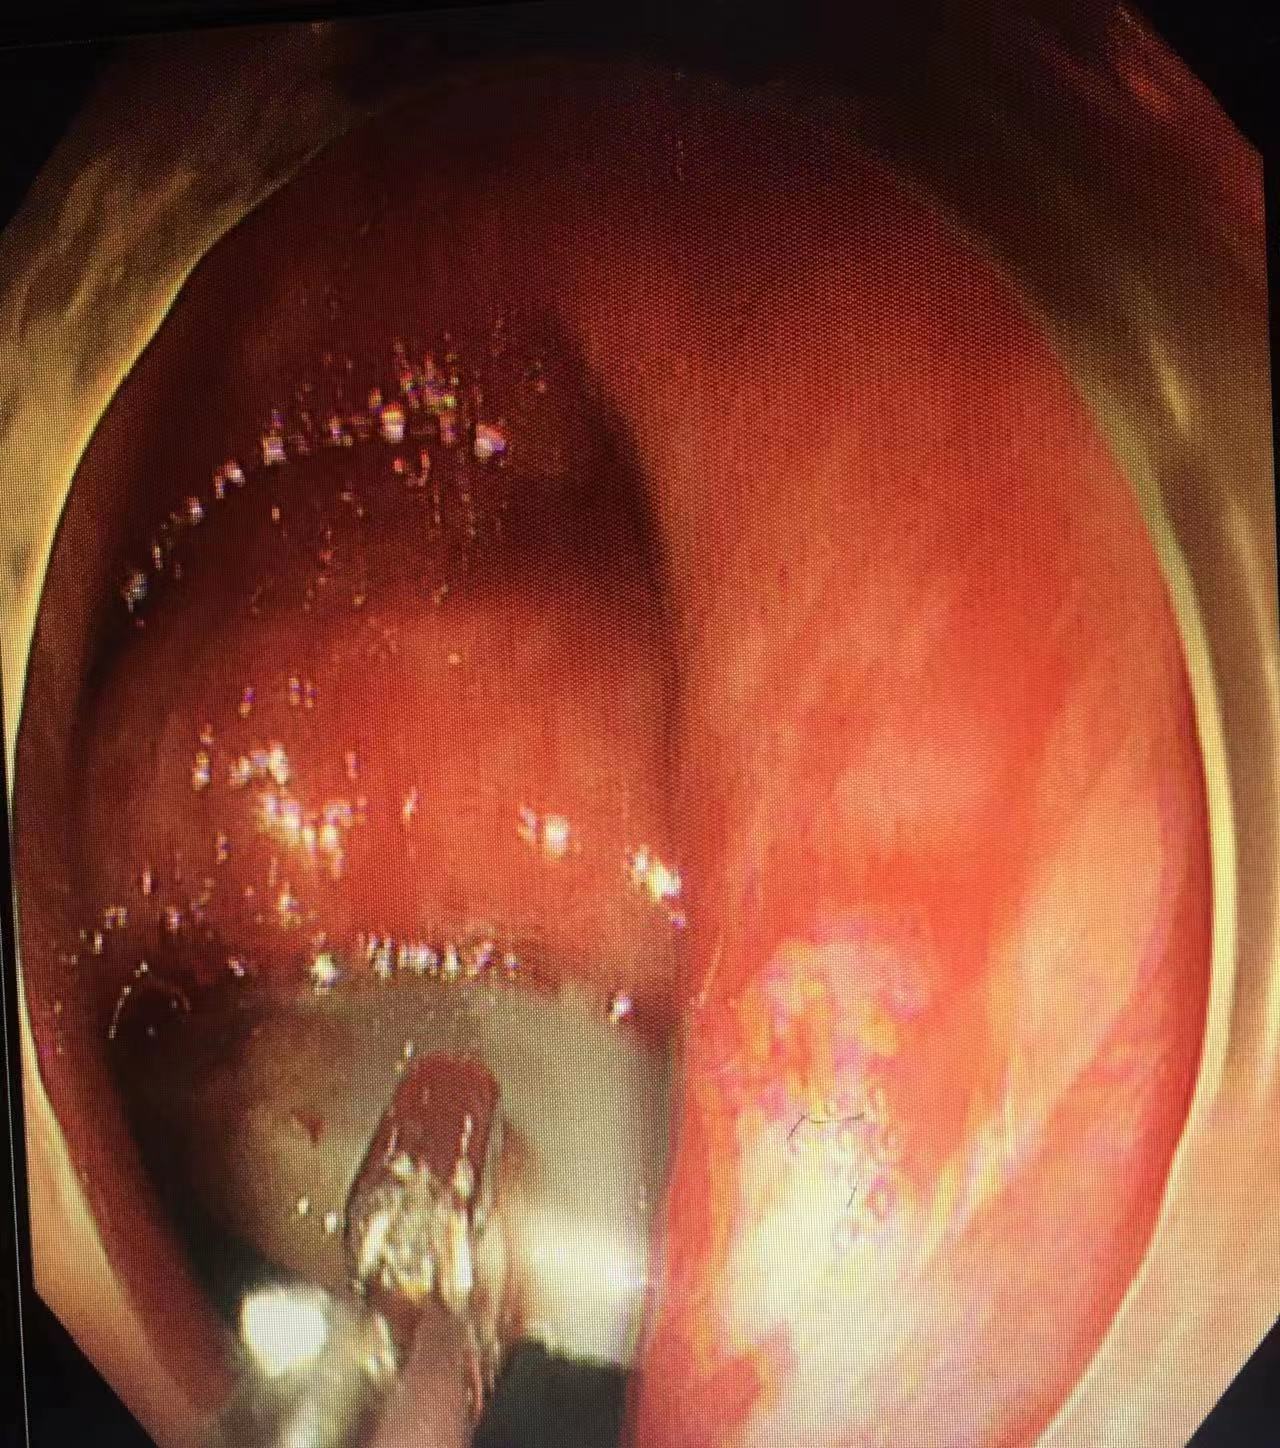

吕培华医生尝试使用圈套器、异物钳、鳄嘴钳等多种器械设备,反复不断地调整着角度、方向,在狭小的肠道空间中艰难地让异物沿着生理曲度挪移。每一分每一秒,都透着紧张与专注。在她的全神贯注与不懈努力下,异物一点点往肛门口移动。

半个小时后,异物终于被成功从患者肛门取出,原来是个拖把把头,各种危机也随机解除。此时,室内虽有冷气,吕培华的后背依然被汗水打湿。